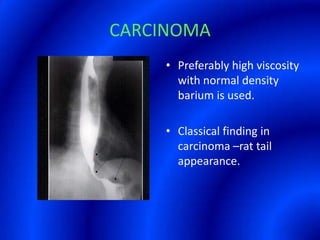

This document provides information about a barium swallow procedure. It begins with an introduction and overview of the embryology and anatomy of the pharynx and esophagus. It then describes the procedure itself, including preparation, technique, views obtained, and indications. Specific conditions that may be examined include pharyngeal and esophageal webs, foreign body impaction, scleroderma, dysphagia, mediastinal masses, and carcinoma. Diagrams are provided to illustrate normal anatomy and various pathological findings.